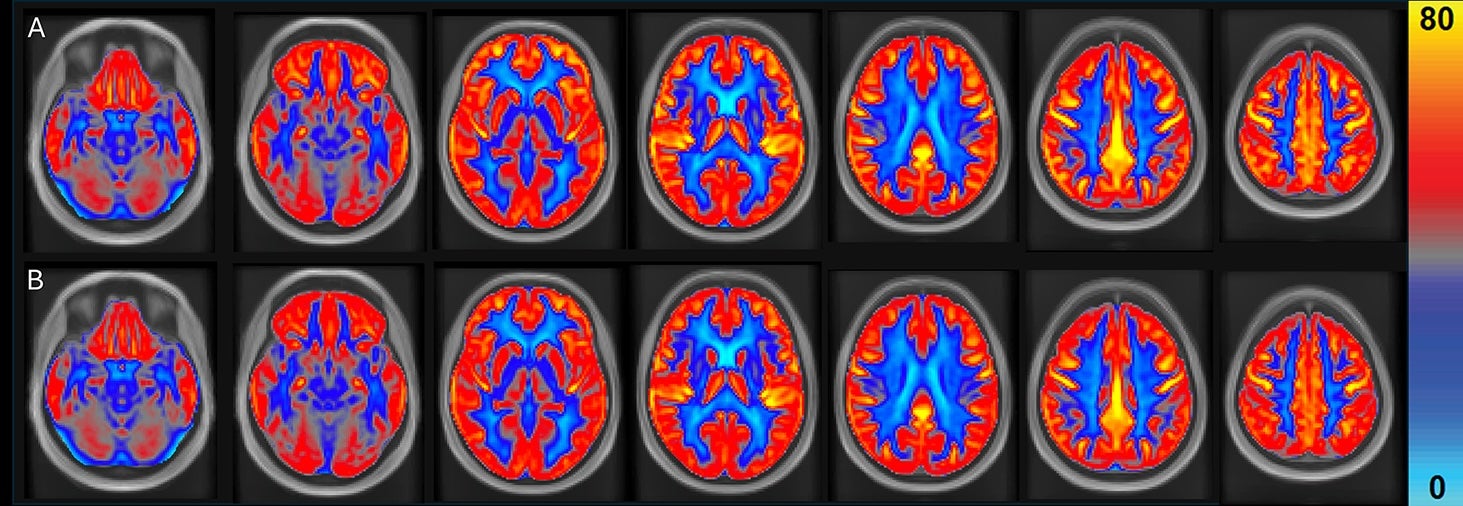

Their cognitive performance was analyzed using a computer test known as the Cambridge Neuropsychological Test Automated Battery and the researchers also used MRIs to investigate the effects of eating peanuts on brain health.

“However, in contrast to our two earlier studies that reported only regional changes in cerebral blood flow, the current findings also demonstrate increases in global cerebral blood flow and gray matter cerebral blood flow of 3.6 percent and 4.5 percent, respectively,” Joris and his team wrote with the current findings.